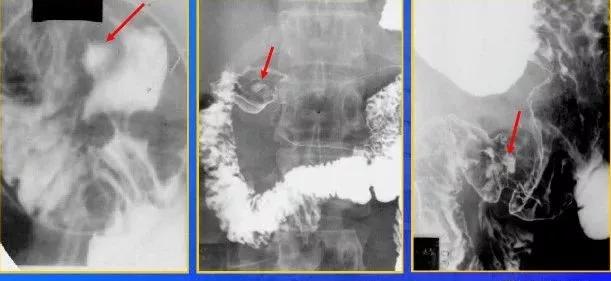

十二指肠球部溃疡,正位片龛影及黏膜纠集

十二指肠球部溃疡,球部变形

十二指肠球线性溃疡。上胃肠道双对比相示变形的十二指肠求内已垂直于肠纵轴的短线条状龛影及纠集的黏膜纹